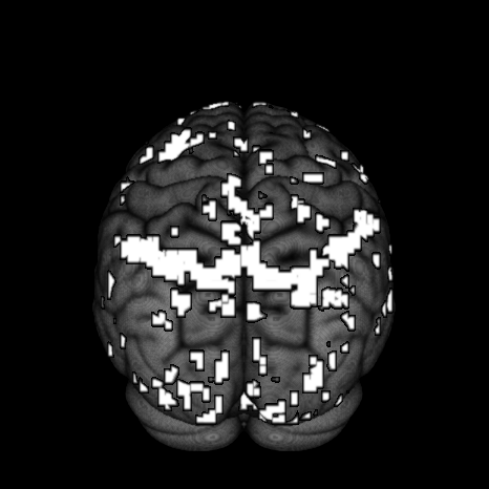

Finally, we look at the effect of fame using thresholded PPMs. The activation threshold is set to of the global mean value, and the probability threshold is set to . Figure 9 shows the activation regions projected onto the pial surface. We can see that there is a match in terms of a majority of activation regions inferred from SVARO and PMCMC. A closer look reveals that PMCMC tends to make more scattered predictions across the posterior regions of the brain. The number of activation regions from PVB are far greater than the number obtained from the other two approaches, and are more widely dispersed across the brain. From our simulation study results, we suspect that these scattered activated regions are likely false positives.